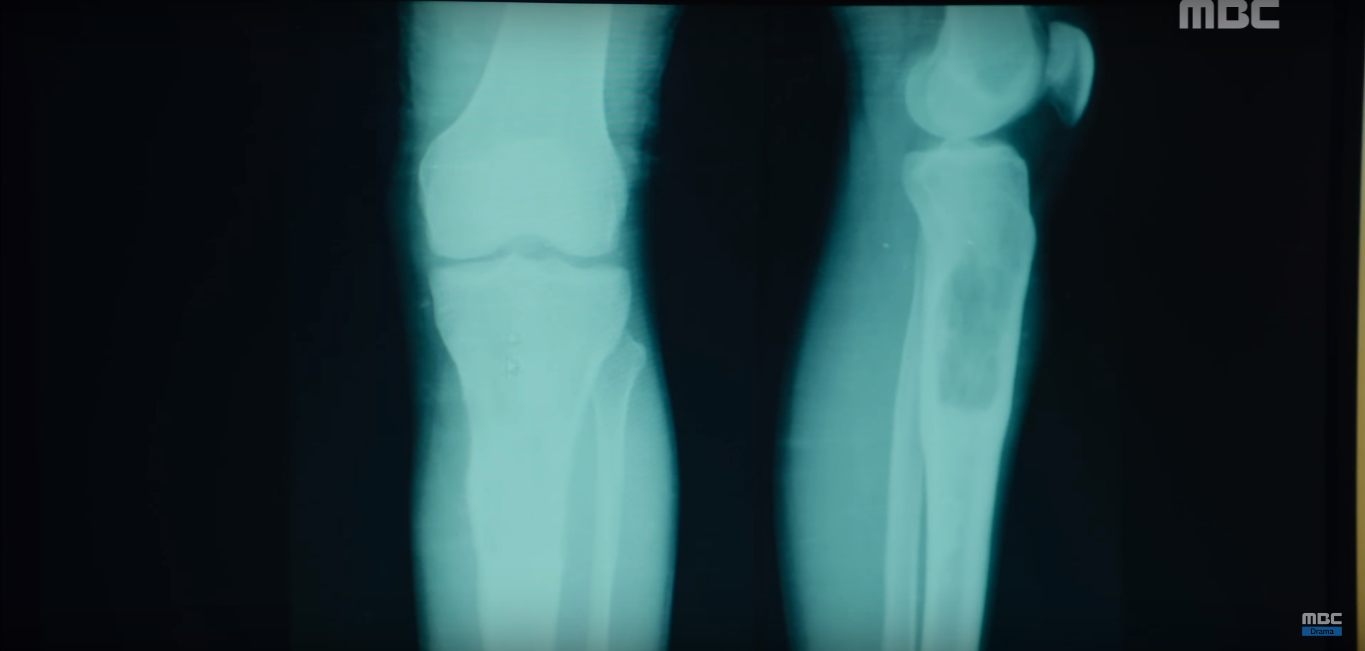

Bác sĩ Choo Won Gong nhận ra bác sĩ Song đã bị ung thư xương ác tính.

Ảnh phim chụp X - Ray xương của bác sĩ Song Eun Jae.